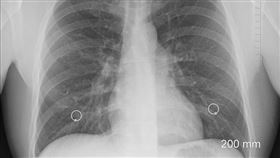

恐怖!6個台灣人有1人因「肺病」離世

根據衛生福利部的統計,2021年離世的18萬名國人中...